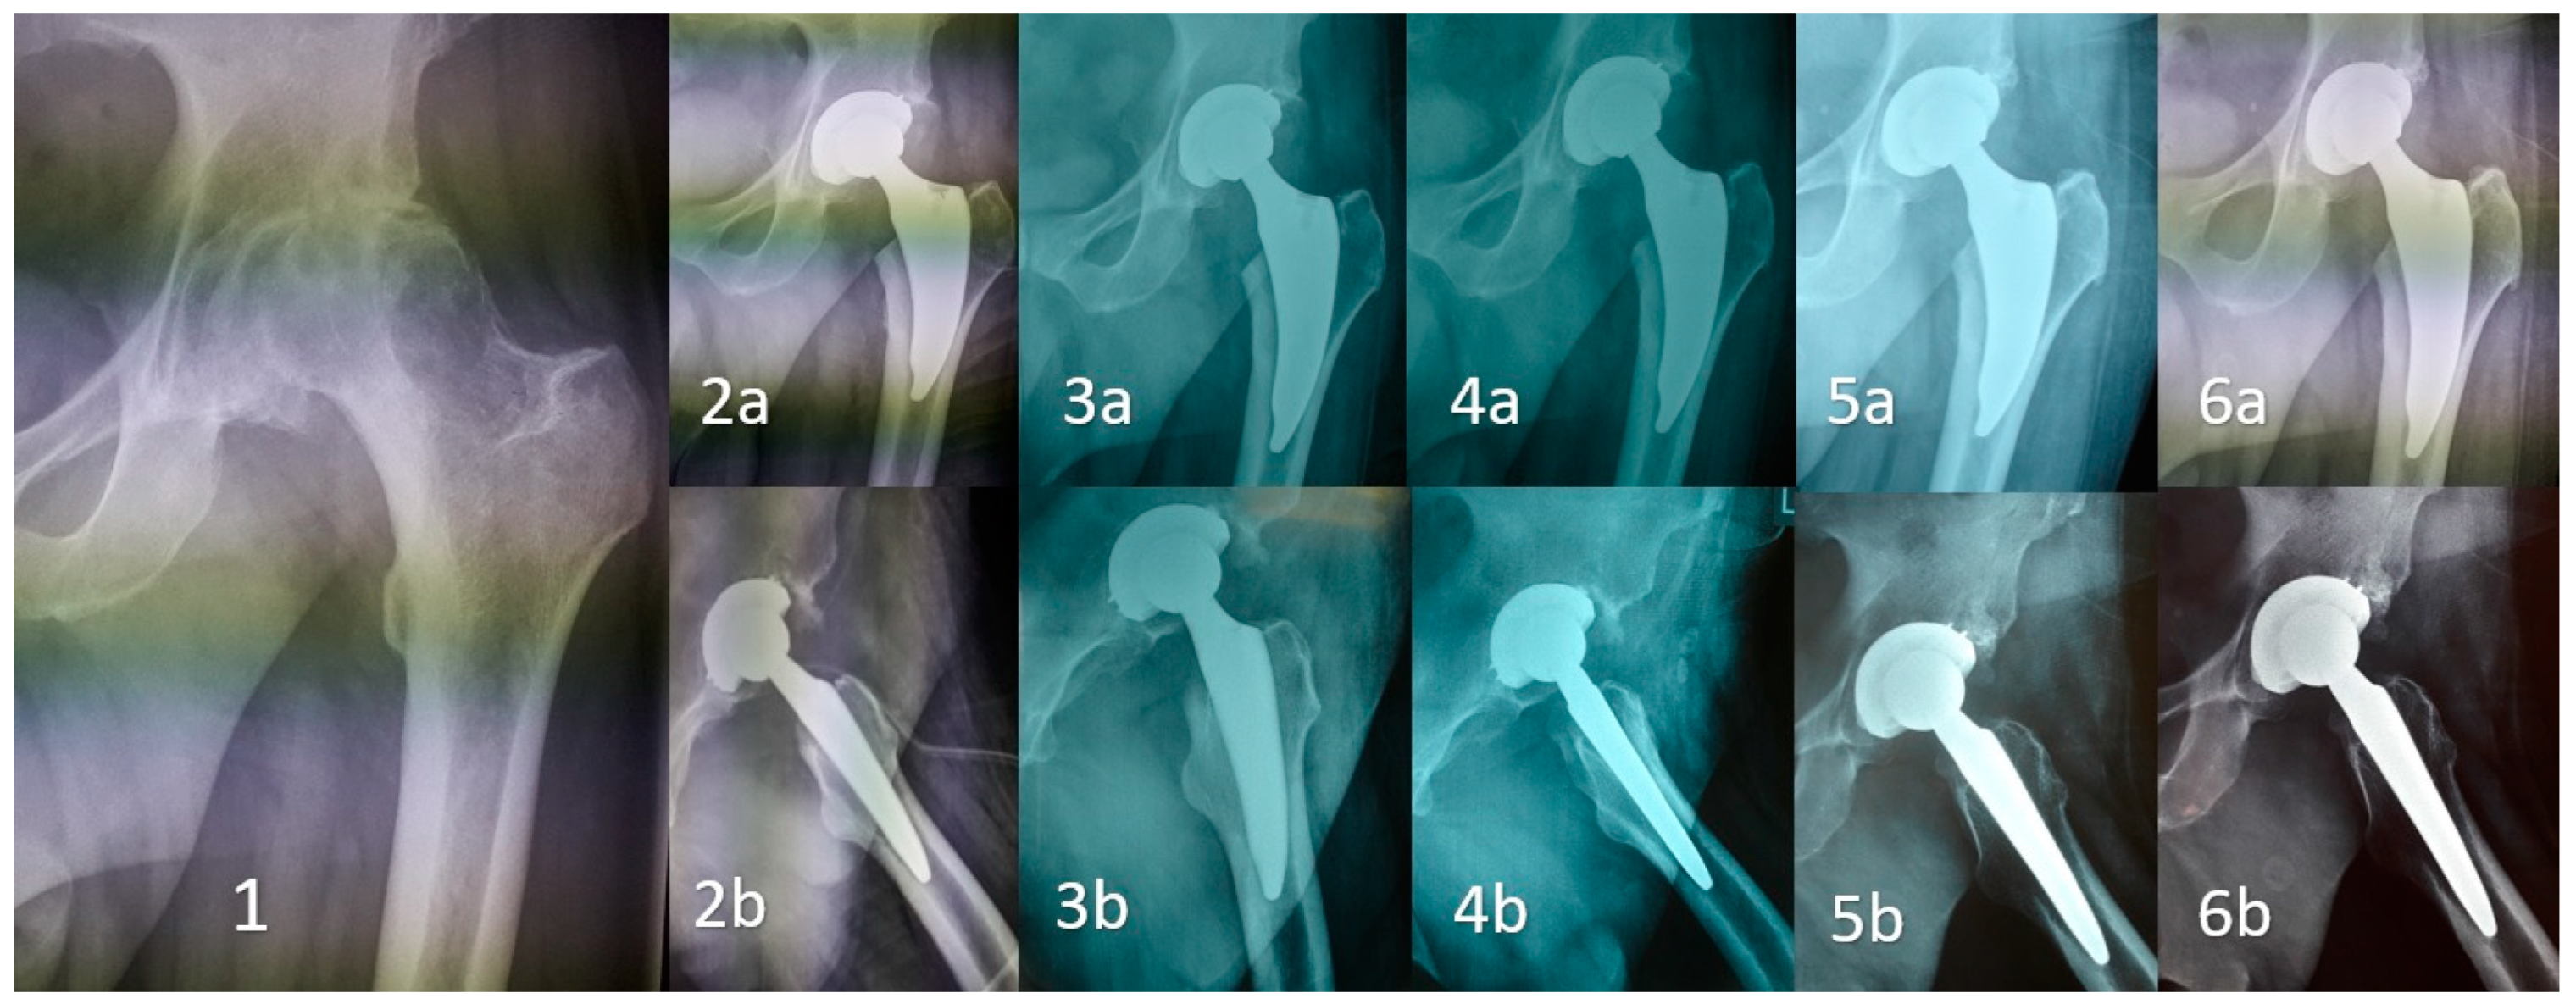

Early Clinical and Radiographic Outcomes of Total Hip Arthroplasty with DELTA ST-C Cup and MINIMA S Stem

2. Methods

3. Results